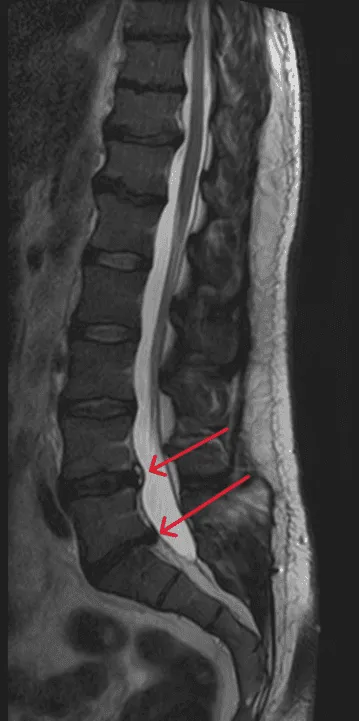

MRI scan showing spinal instability with bone slip, highlighted by arrows and labeled in red text.

Spinal Instability

MRI of the lumbar spine with red arrows indicating areas of interest.

Recurrent Disc Herniation

Herniation reoccurs at the same or adjacent level despite disc replacement.